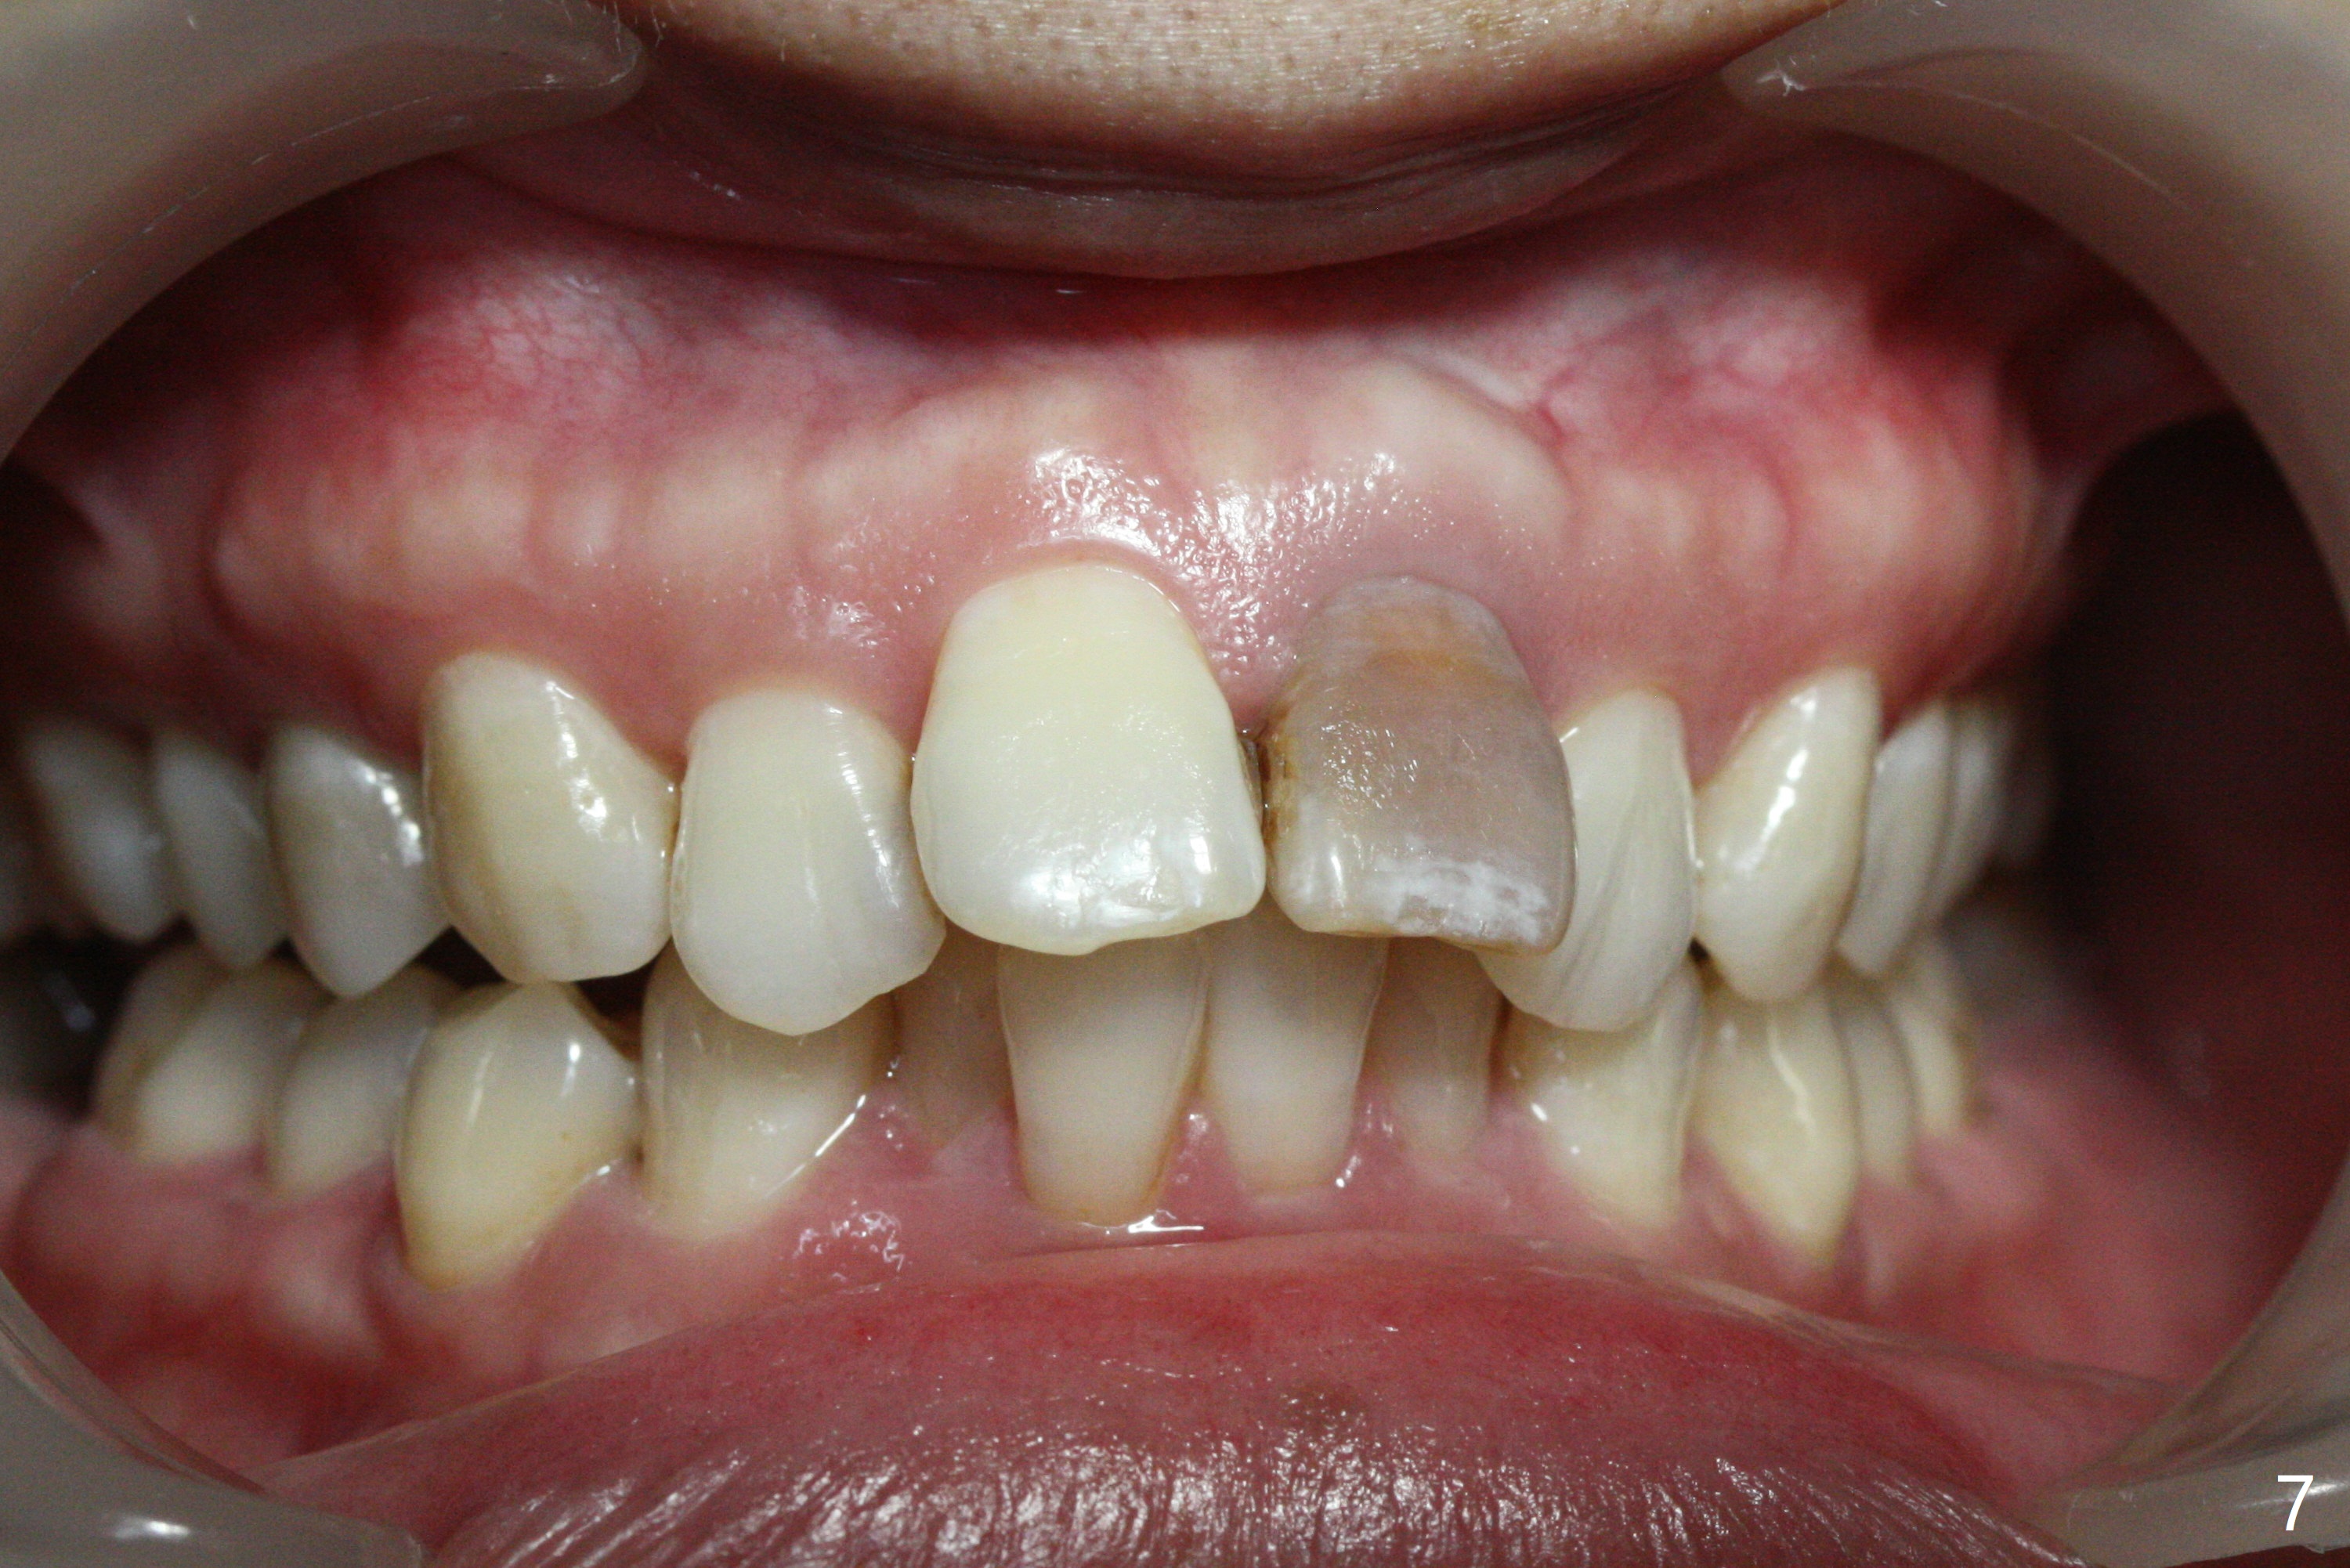

A 41-year-old woman requests ortho, bleach and replacement of 2 lower molars (L7s). The lips are protrusive (Fig.1,3), which is seemingly due to the underlying protrusive anterior teeth (Fig.4,5). Cephalometric tracing shows that SNA and SNB are both 87º (Fig.12), suggesting extraction. When the protrusive teeth are distalized, pay attention to move the upper dental midline to the right (Fig.2). BWs show subgingival calculus. SRP is required. Internal bleaching will be conducted for UL1 (Fig.7,11). Distalization is accomplished with extraction of 2 upper 1st bicuspids and using L8s as anchors so that no implants will be necessary for L7s. But the patient would rather have 2 of the lower 2nd molars for mastication. It appears that extraction of 4 bicuspids is pending (Fig.6-11). Supraeruption of U7s (Fig.6,8 arrows) will be corrected with banding.